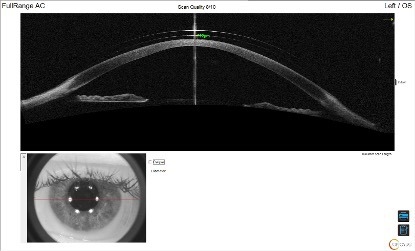

Based on the findings of a diagnostic scleral lens fitting, a trial lens was ordered. To improve the accuracy of the fit, anterior segment optical coherence tomography (OCT) technology (Optovue Solix, Visionix, USA) was utilized in conjunction with slit lamp examination to evaluate the central clearance, limbal clearance, and edge alignment. Slit lamp evaluation of the initial trial lens revealed an adequate central clearance with no areas of central touch, inferior decentration with thin limbal clearance superiorly and excessive limbal clearance inferiorly, and slightly flat edge alignment both temporally and superiorly. When evaluated via OCT imaging, the central clearance was measured to be 222 µm as seen in Figure 2. The superior limbal zone was clearing adequately, while the inferior limbal zone showed excessive clearance.

Anterior segment OCT can be an invaluable tool to assist with scleral lens fitting and improve lens accuracy and alignment. This straightforward scleral lens fitting case demonstrates the ease of scleral lens fitting with OCT assistance. Several Optovue Solix scan protocols can be useful, including Corneal Mapping (full corneal epithelial, stromal, and pachymetry mapping), to achieve corneal topography and select the initial diagnostic lens. FullRange AC, which can capture the entire anterior chamber in a single scan, can help image the central and limbal zones, and the Cornea Angle scan, which quantifies the openness of the iridocorneal angle, is useful for a more magnified limbal zone image as well as edge alignment.